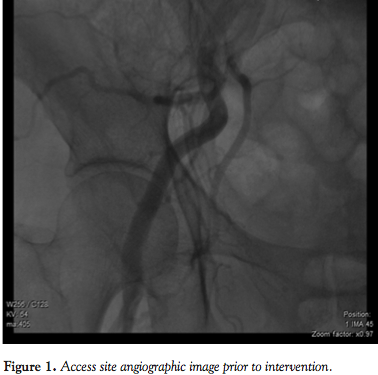

Standard procedure. Femoral artery cannulation for CoreValve (Medtronic) delivery is routinely performed utilizing the crossover technique. This includes a 5 Fr pigtail introduction contralaterally into the mid portion of the ipsilateral femoral artery in order to attain puncture of the arterial wall for the main access-site cannulation (Figure 1). Subsequently, the 10 Fr Prostar XL (Abbott Vascular) closure device is inserted and its two pairs of suture needles are brought out through the arteriotomy site and secured. Finally, the CoreValve Revalving System is introduced and implanted, as described elsewhere.10